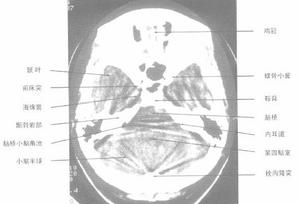

側顱底解剖圖側顱底指以鼻咽頂壁中心,向前外經翼齶窩達眶下裂前端,向後外經頸靜脈窩到乳突後緣兩條假想線之間的三角區。側顱底區常見的腫瘤有鼻咽癌、中耳癌、中神經與面神經鞘膜瘤、腦膜瘤、畸胎瘤、先天性膽脂瘤等;其中重要而複雜者為頸靜脈球體瘤。頸靜脈球體瘤又稱血管球瘤。

顱底劃分,尚未統一,所謂側顱底指以鼻咽頂壁中心,向前外經翼齶窩達眶下裂前端,向後外經頸靜脈窩到乳突後緣兩條假想線之間的三角區,該區包括頸內動脈孔、頸靜脈孔、卵圓孔,棘孔、莖乳孔和由各孔穿行的腦神經和血管,另外還有顳頜關節,咽鼓管骨部等,側顱底區常見的腫瘤有鼻咽癌,中耳癌、聽神經與面神經鞘膜瘤,腦膜瘤、畸胎瘤、先天性膽脂瘤等,其中重要而複雜者為頸靜脈球體瘤。頸靜脈球體瘤又稱血管球瘤,是一種多發於中年以上婦女的良性中流,有家族發病傾向。